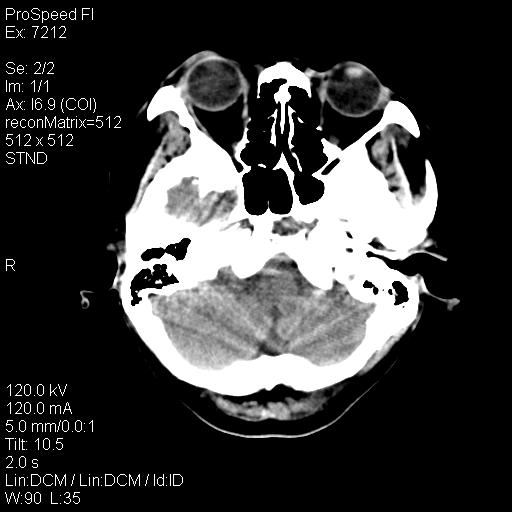

右额叶脑沟变浅,脑表面见新月形稍高密度影,考虑慢性硬膜下出血可能。

1)考虑左侧额颞部及右侧额部慢性硬膜下血肿(或硬膜下积液)。2)颅骨骨髓瘤不排除;建议行进一步检查。

1)右侧半卵圆中心腔隙性脑梗塞。2)考虑左侧额部慢性硬膜下血肿(或硬膜下积液)。3)颅骨骨髓瘤不排除;建议行进一步检查。